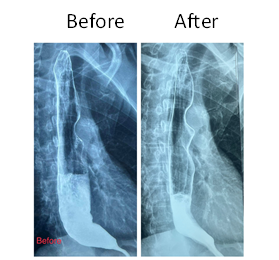

There were no major adverse events in the intra-operative and immediate post-operative period in all cases. Patient B had mild reflux symptoms (GerdQ 5/18). Their symptoms, if any, were once again graded according to the Eckardt system. The comparison between the pre-procedural and post-procedural score showed excellent results in relieving the symptoms and significant weight gains (Table 2). Barium swallow at one month post-operation revealed significant reduction in stasis and free flow of barium across GEJ (Figures 3 & 4).

Fig.4- Pre-procedural and 1 month post-procedural barium study of Patient B